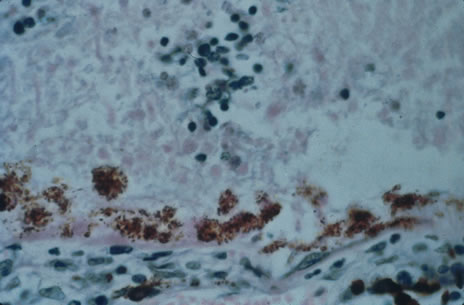

Any cell type may be infected, appearing larger than normal (cytomegalic) and demonstrating eosinophilic intranuclear “owl's eye” and smaller intracytoplasmic viral inclusion bodies, which are better seen with Giemsa or Papanicolaou's stains (Fig. 8). Histologic examination of tissue specimens, including bronchoalveolar lavage fluid and urine, may be useful for diagnosis.

Fig. 8. Typical lesion of cytomegalovirus (CMV) produces retinal necrosis with large cells possessing owl's eye inclusions.